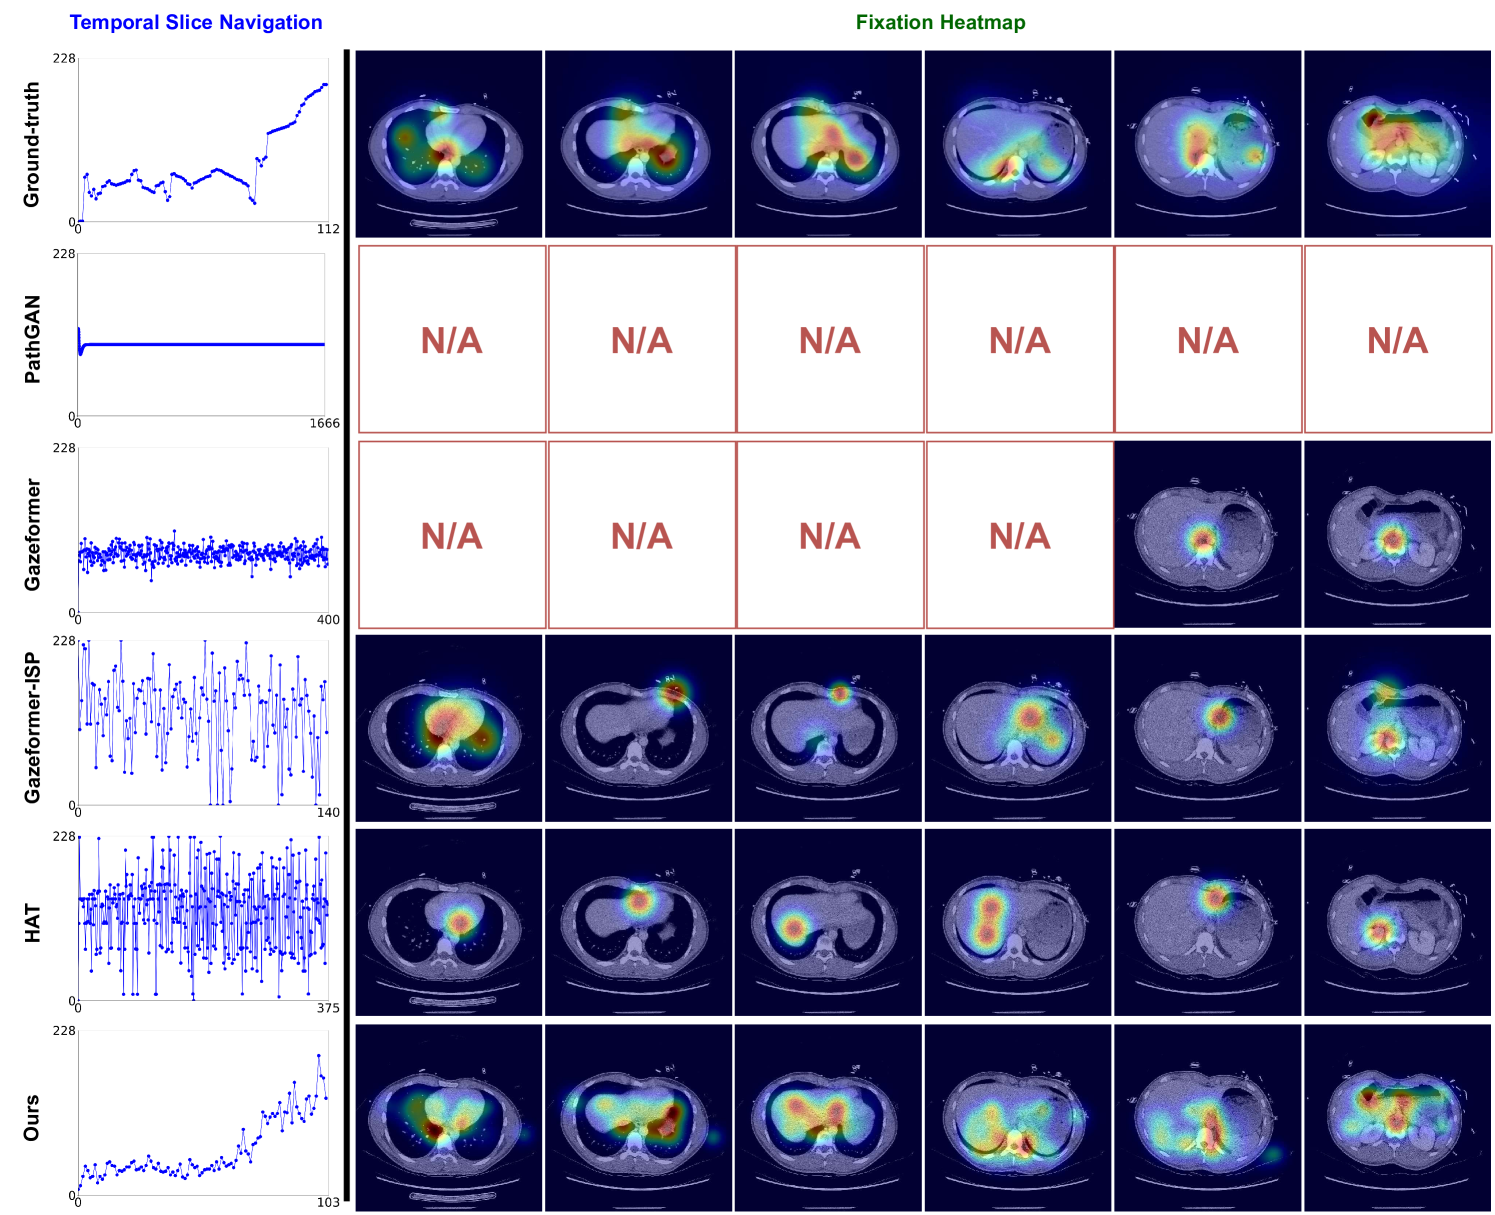

Refer to caption

Figure 5: Qualitative comparison of our method and other SOTA methods, HAT and GazeformerISP. The Temporal Slice Navigation column shows the predicted scanpath over time, with the y-axis representing slice numbers (out of 89 total) and the x-axis showing fixation indices. For example, the ground truth has 105 fixations, with fixations move through depth from the earliest to the last slices. The Fixation Heatmap columns present the fixation heatmaps, illustrating regions of interest from which the corresponding gaze positions are sampled. The visualized CT slices for these heatmaps are selected between slice numbers 40 and 50. We observe that CT-Searcher can capture the navigation pattern of radiologists. Especially, the orange area indicates that the back-and-forth scanning behavior of radiologists has been successfully captured by CT-Searcher.

We present qualitative results in Fig. 5 to demonstrate the effectiveness of our proposed method. The results reveal clear performance differences across evaluation aspects. In the temporal slice navigation plots (Fig. 5, left), CT-Searcher captures similar temporal dynamics to the ground-truth, while baseline methods (GazeformerISP and HAT) exhibit erratic, high-variance patterns. Notably, the orange areas show that CT-Searcher replicates the non-linear behavior characteristic of experienced readers, who frequently navigate back and forth through the volume to revisit suspicious regions. The fixation heatmap visualization (Fig. 5, right) demonstrates that CT-Searcher produces more accurate attention distributions compared to other methods. These qualitative findings confirm that our approach successfully replicates the complex visual search patterns of radiologists during CT interpretation, representing a significant advancement in 3D medical scanpath prediction. We provide additional qualitative results in Appendix F.